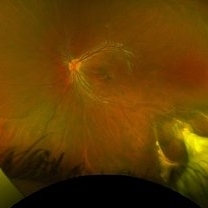

Ocular Toxocariasis

Jul 4 2024 by Brandon I Fram, MD, BS

4 yo with toxocariasis-related peripheral granuloma with adhesion to the macula and macular subretinal fibrosis. Positive Toxocara titers.

Condition/keywords: toxocara canis, toxocara granuloma, toxocariasis